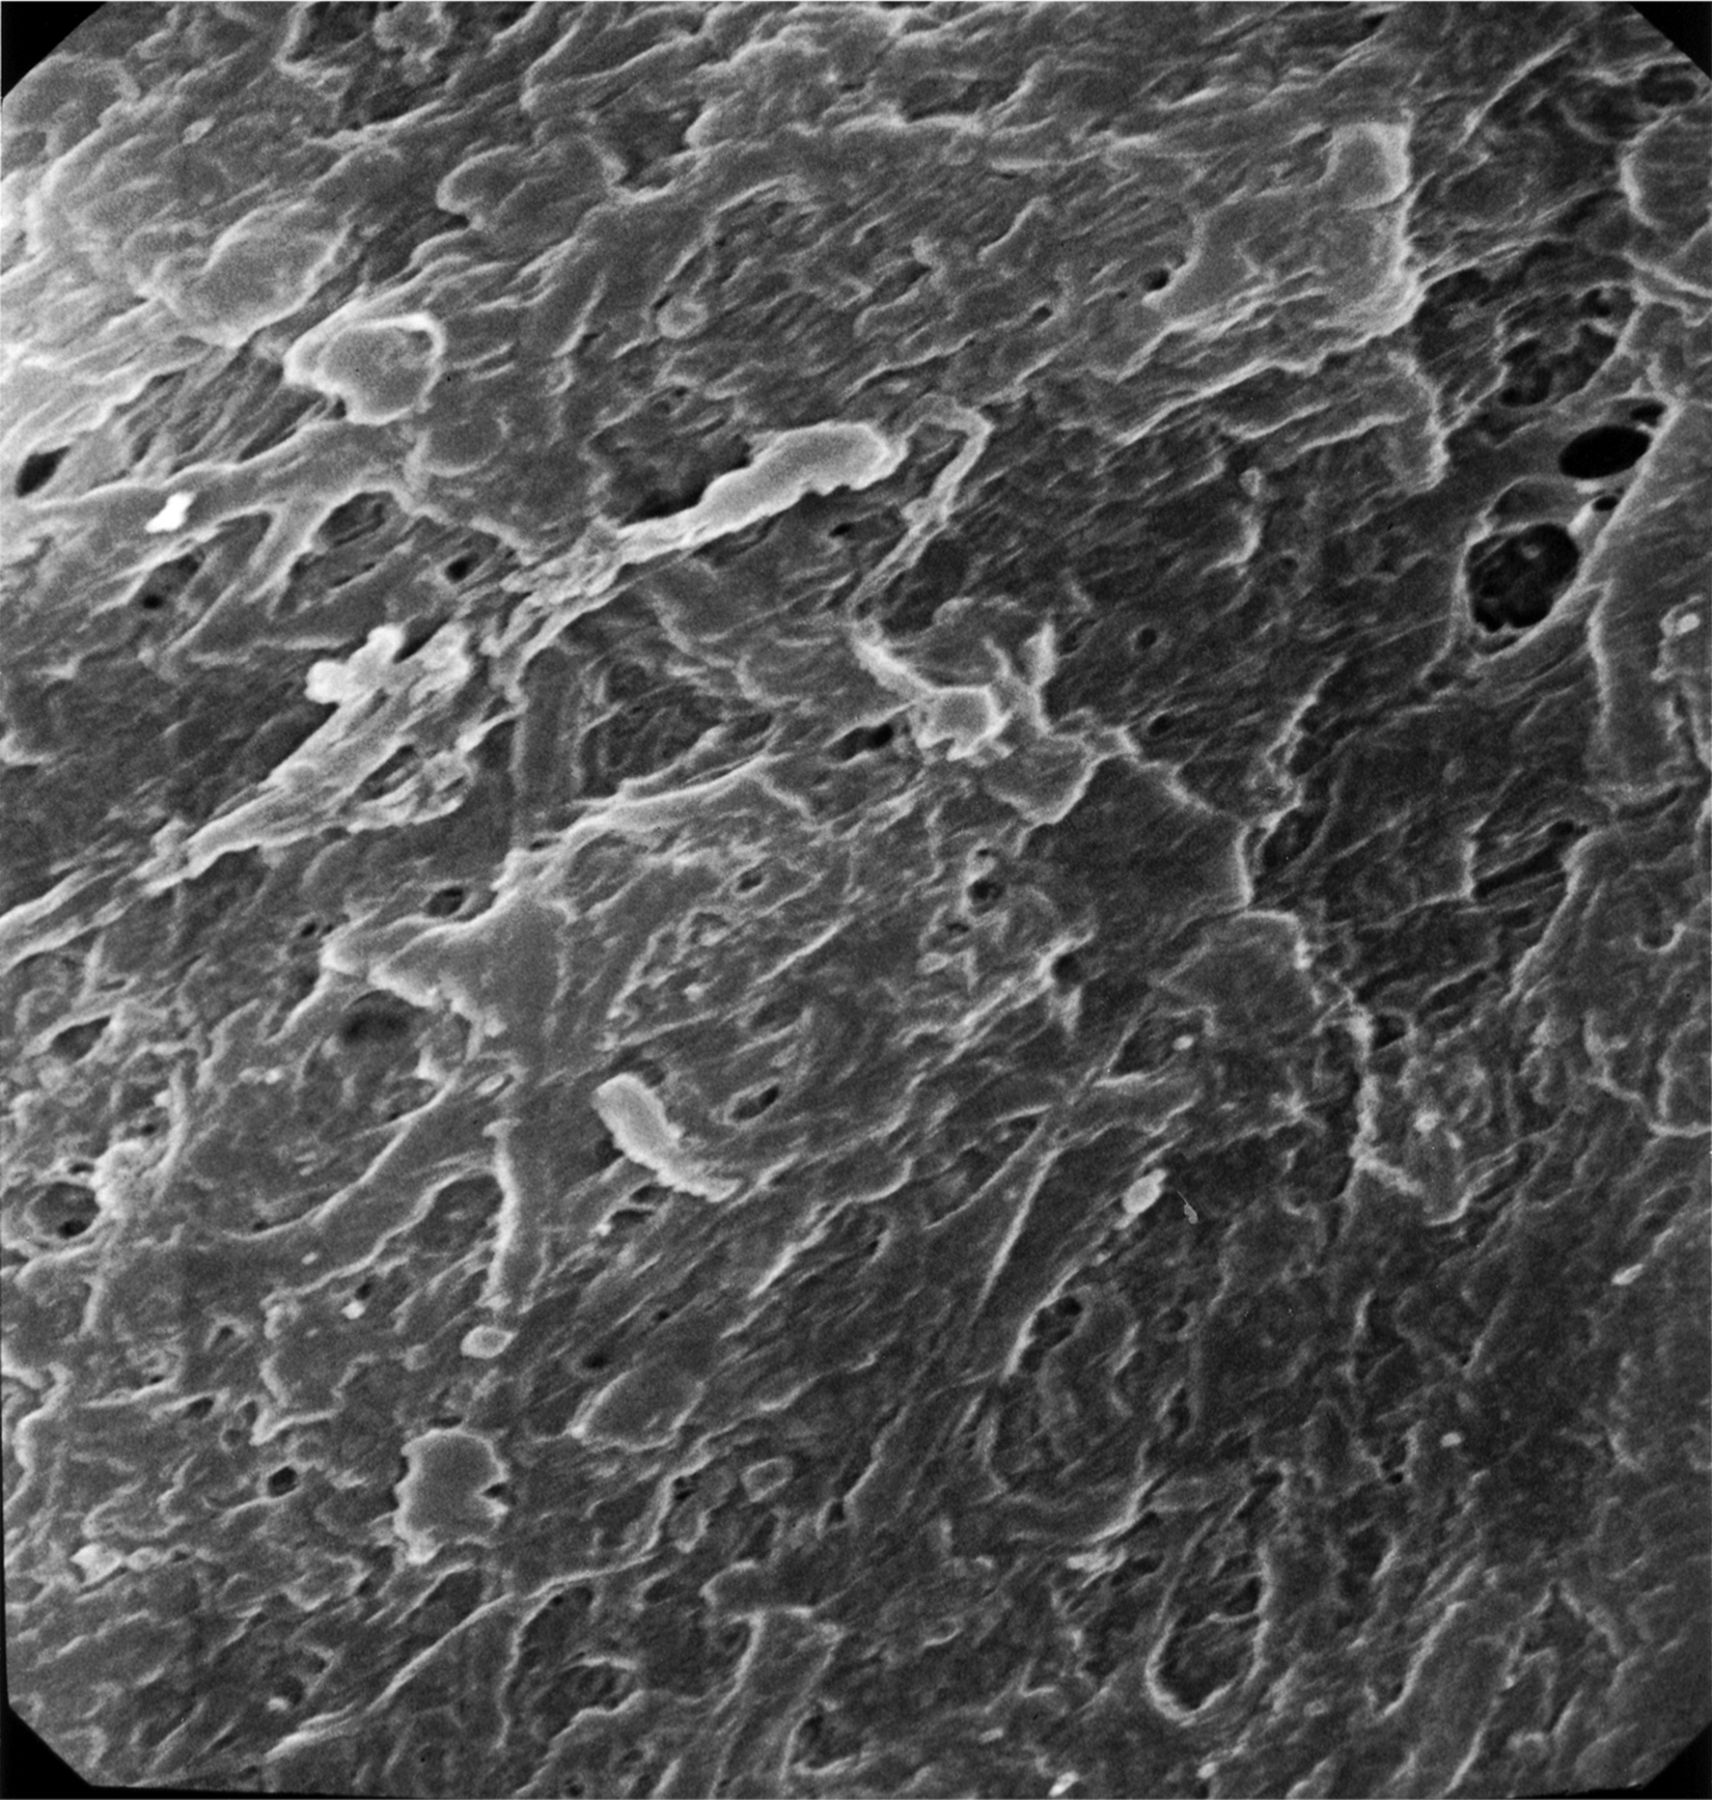

扫描电子显微镜分析。

先前的研究使用光学显微镜和后续相关早期血管成像特点给重要的见解血栓性的组织学病变,12,22尽管他们有限无法分析血栓的超微结构。这个问题最近被解决通过扫描电子显微镜(SEM)分析血栓栓塞材料从大脑检索和急性缺血性中风患者的颈动脉。23

两个不同的结构模式与SEM可以认出:1)血栓展示先进成熟,所有的血栓性元素是如此密集集成单个实体没有清晰可辨的(图2),表明心脏稳定位置,持续暴露在剪切流;和2)血栓显示不同的纤维蛋白,红细胞被困,表明相对宽松的交联,一个活跃的地区特点的血栓仍在成熟的过程中,可能停滞的地区形成和再循环(图3)。这些模式被认为在不同比例在不同的患者。在某些情况下,可以联系具体的超微结构的研究结果推测病因的中风。值得注意的是这样一个广泛的血栓被恢复。

扫描电子显微镜图像3000×显示了一个紧密集成的血栓性组件的交联结构,即。,红色细胞、纤维蛋白和血小板,如此密集的个人实体不再明显,合并成一个坚固的结构。